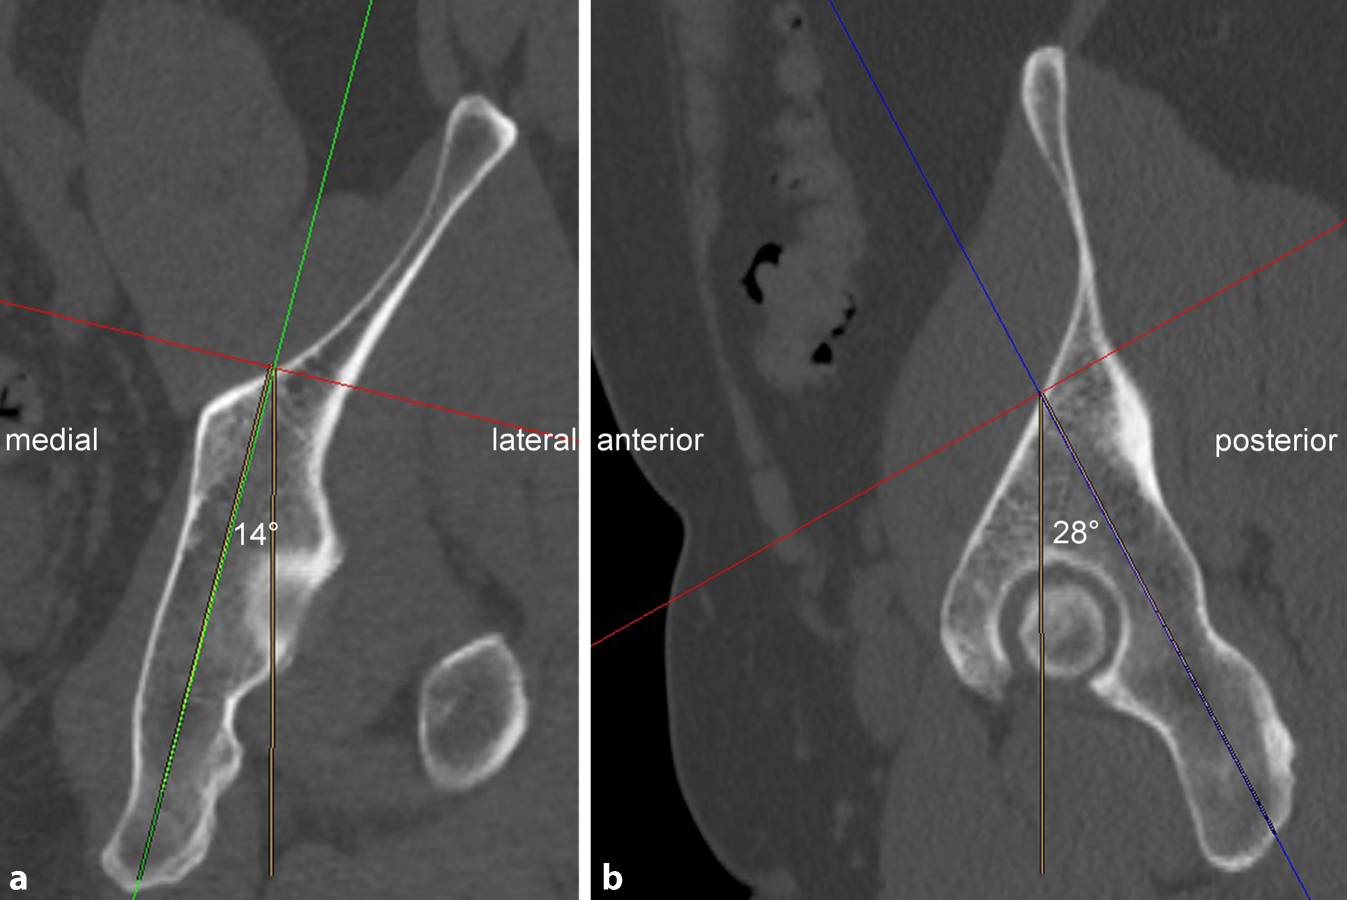

Fig. 1

a Injury mechanism of anterior column with posterior hemitransverse fractures (ACPHF). ACPHF typically result from force transmission via the greater trochanter and the femoral neck with the hip joint in extension. Due to the anteversion of the femoral neck the anterior column is affected first and frequently shows a multifragmentary fracture pattern. Further protrusion of the femoral head leads to a simple posterior hemitransverse fracture and a fracture component in the transition zone between the anterior column and the quadrilateral plate. The quadrilateral plate therefore remains in osseous continuity with the posterior column. These two fracture components allow for an internal rotation of the posterior column as a result of the medial protrusion of the femoral head. Accordingly, the quadrilateral plate is not separated from the two acetabular columns. It is internally rotated in osseous continuity with the posterior column. b Fracture components of ACPHF. The injury mechanism described in a results in the typical fracture patterns of ACPHF with the following fracture components and characteristics: multifragmentary or comminuted anterior column fracture; simple posterior hemitransverse fracture; internal rotation of the posterior column and the attached quadrilateral plate; impaction of the articular surface of the superomedial dome (“gull sign”). c “Gull sign”: impaction of the articular surface of the superomedial dome results from force transmission via the femoral head. The radiological appearance of this impaction has been described as “gull sign” referring to children’s style of drawing sea gulls. The “gull sign” is associated with a poor outcome after open reduction and internal fixation of acetabular fractures [1315]